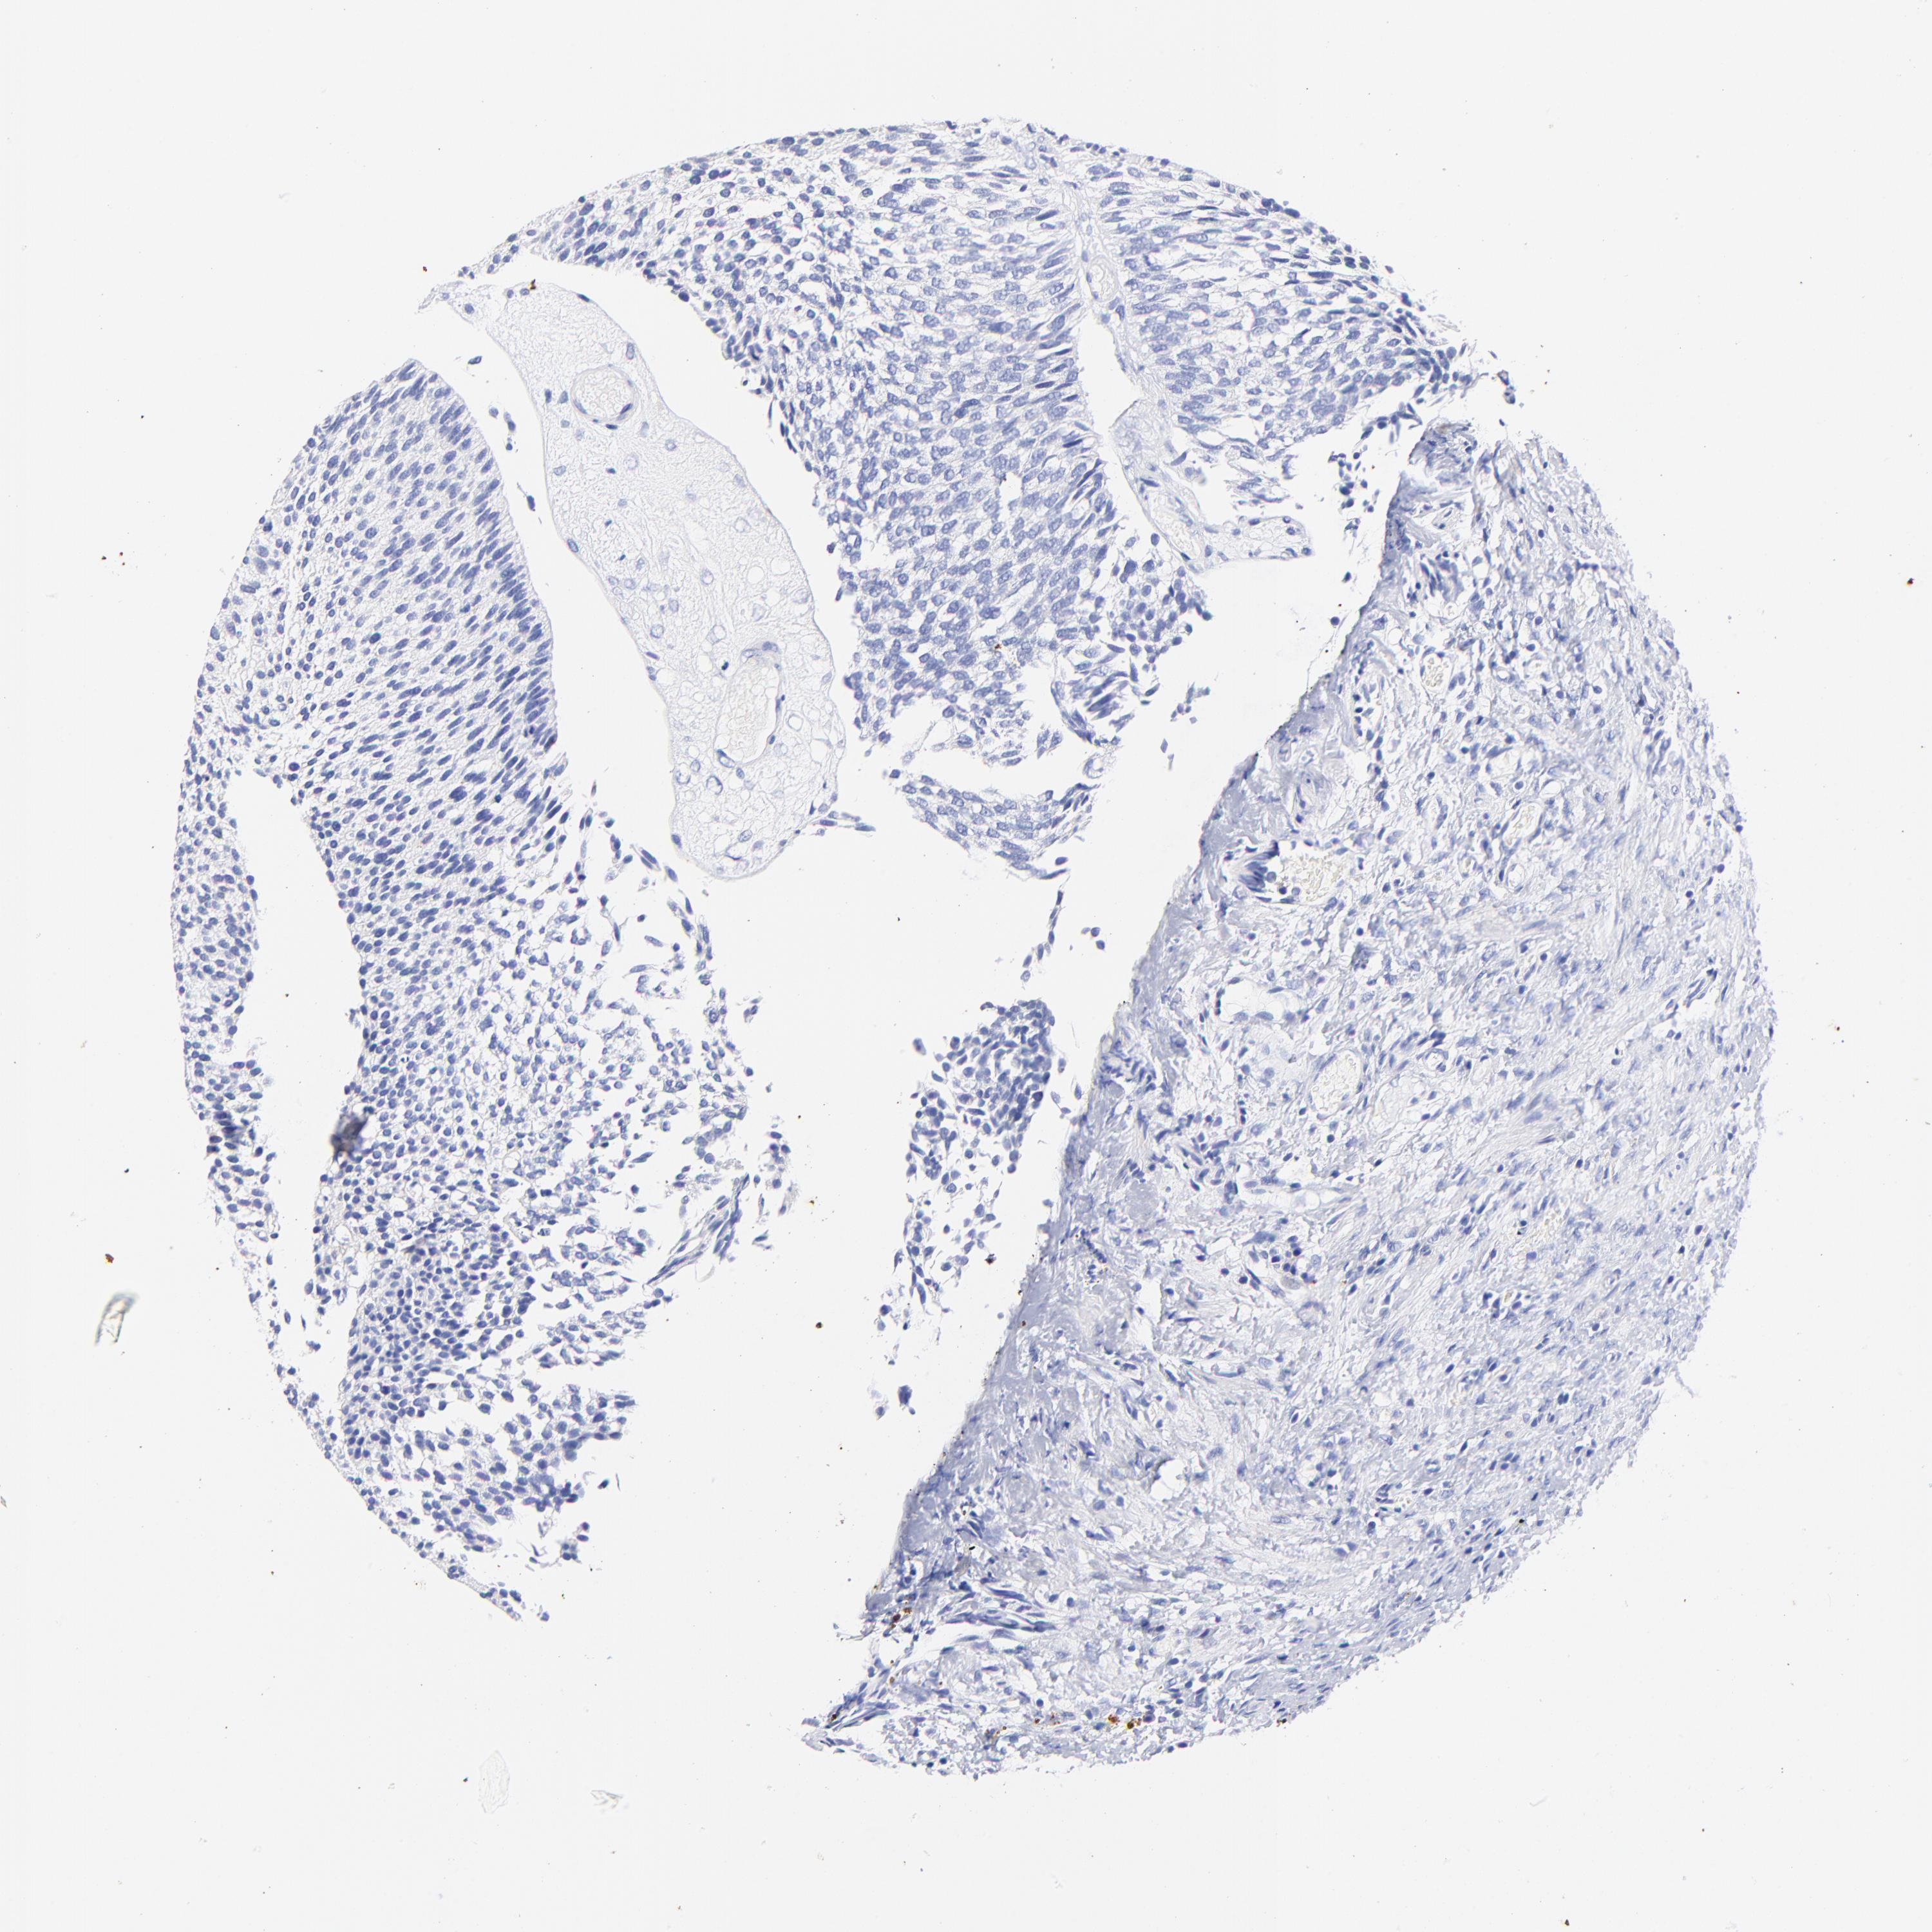

UROTHELIAL CANCER - Protein expressioni

A mouse-over function shows sample information and annotation data. Click on an image to view it in a full screen mode. Samples can be filtered based on level of antibody staining by selecting one or several of the following categories: high, medium, low and not detected. The assay and annotation is described here.

Note that samples used for immunohistochemistry by the Human Protein Atlas do not correspond to samples in the TCGA dataset.

Antibody stainingi

Antibody staining in the annotated cell types in the current human tissue is reported as not detected, low, medium, or high, based on conventional immunohistochemistry profiling in selected tissues. This score is based on the combination of the staining intensity and fraction of stained cells.

Each image is clickable and will lead to virtual microscopy that enables deeper exploration of all samples and also displays staining intensity scores, fraction scores and subcellular localization as well as patient and tissue information for each sample.

Antibody HPA003074

Staining

High

Medium

Low

Not detected

Intensity

Strong

Moderate

Weak

Negative

Quantity

>75%

75%-25%

<25%

None

Location

Nuclear

Cytoplasmic/membranous

Cytoplasmic/membranous,nuclear

Urothelial carcinoma, High grade

Urothelial carcinoma, Low grade

Adenocarcinoma, NOS